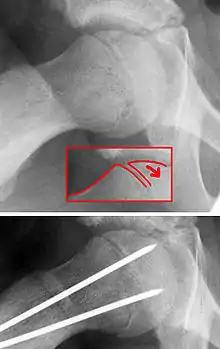

La enfermedad SCFE, se puede tratar con clavos externos in situ o con clavos y reducción abiertos.[14]